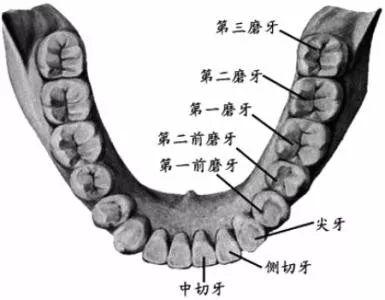

智齒,學(xué)名三大臼(jiù)齒,又叫做第三磨牙。

雖然叫做智齒,但其實(shí)和智商毫無(wú)關(guān)系...只是一般在 18 歲后長(zhǎng)出來(lái),正處于人類(lèi)智力發(fā)育的鼎盛期而得名(小時(shí)候看鄭淵潔的《智齒》,一直對(duì)自己沒(méi)有長(zhǎng)智齒而耿耿于懷,現(xiàn)在,悔之晚矣...)。

人類(lèi)在進(jìn)化過(guò)程中,進(jìn)食的食物是越來(lái)越精細(xì),頜骨(就是你的下巴)越來(lái)越短,但牙齒不會(huì)減少,有的牙齒就沒(méi)有空間長(zhǎng)出來(lái)。嚴(yán)肅的推斷出「智齒長(zhǎng)不好,說(shuō)明你臉小」(強(qiáng)行安慰一波長(zhǎng)阻生智齒的人)...